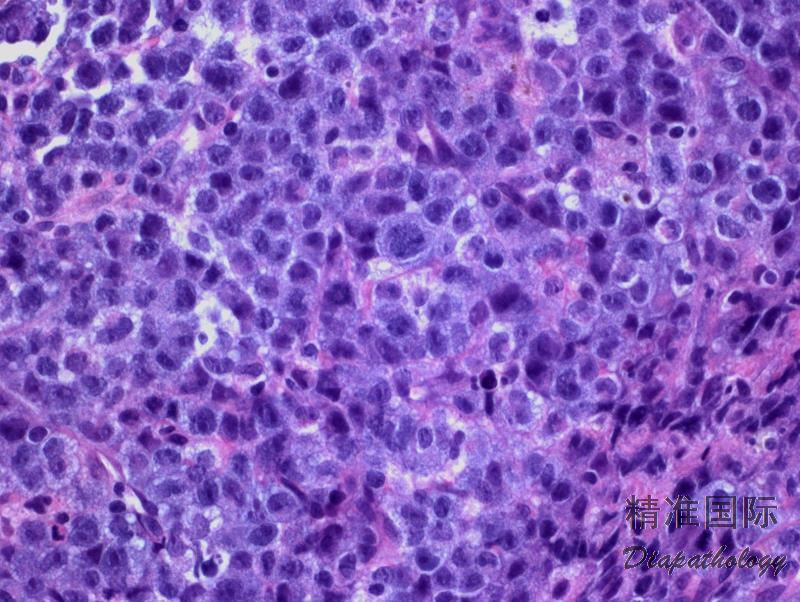

肿瘤细胞形态谱系较宽,从主要是较小细胞到全是异性大细胞。根据肿瘤细胞大小、形态、浸润方式和背景细胞成分等分为多种模式。多数病例(常见模式,占 60%)由多形性大细胞构成,细胞胞质丰富、常透明、嗜碱性或嗜酸性,核染色质通常细块状或散在分布,可有多个核仁。此外,还有小细胞模式(5-10%),淋巴组织细胞模式(10%),霍奇金样模式(3%),或混合/复合模式(15%)。偶有病例肿瘤细胞稀少,伴背景粘液样改变,或有很多梭形细胞,呈现肉瘤样改变。无论什么生张模式,都含有数量不等的 CD30+“标志性细胞”,其形态特征为异型大细胞含偏位马蹄样或肾形核,核周常有嗜酸性区域。

免疫表型:CD30+(胞膜和高尔基区,大细胞强阳性,较小的肿瘤细胞可以弱阳性甚至阴性),ALK+(核和胞质、胞质、胞膜),EMA+/-,TIA1+/-,粒酶+/-,穿孔素+/-,CD4+/-,CD43+/-,CD3-/+,CD5-/+,CD7-/+,CD45-/+,LMP-1-, EBER-。

- 普通型 ALCL :最多见(60%)。肿瘤由多形大细胞包括标志性细胞构成,但也可是较单一的卵圆形核细胞混合多形型大细胞,通常呈粘附性生长,可见特征性窦内浸润。